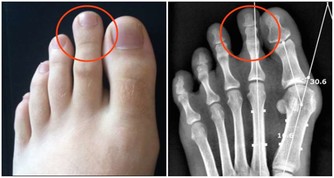

女性每年有20萬人口死於婦科疾病,其實她們不是死於婦科疾病,是死於對自己的無知! 據世界衛生組織對中國婦女的調查:41%的育齡女性患有不同程度的婦科炎症,而已婚女性發病率更高達70%。下面是一位婦產科主任醫師的筆記,讓我們一起看下。 1.女性生殖系統分兩大部分,一部分是外生殖器,另一部分是內生殖器=。 2.子宮是孕育生命的一個重要場所,未孕時子宮有雞蛋那麼大,一旦受孕,子宮像氣球一樣膨脹,等到了分娩,子宮就要收縮回來,也就像拳頭這麼大了,這個時候的子宮就布滿了皺褶和隱窩,也已經不再光滑了,這些皺褶隱窩裡就要殘留垃圾。 ★子宮到底殘留多少垃圾? ①生兒育女的垃圾--羊水垃圾、惡露垃圾 ②夫妻生活垃圾 ③每個月內膜沒脫落干淨的垃圾 ④再加上內源體外源體新陳代謝的垃圾 這些垃圾日積月累,堆積成山,久而久之它就產生了毒素,萬病起源於毒素,也就是現在為什麼有那麼肌瘤啊,囊腫啊,內膜炎啊等等婦科疾病的原因。 以前的人為什麼沒有這麼多毛病呢?那是因為生育多,後一次把前一次的垃圾衝出來,沒有陳年垃圾,加上不斷地母乳喂養,乳腺不斷地疏通,固難以造成阻塞,加上環境因素,婦科疾病沒有現在這麼多。 3.避孕環有沒有傷害? 說沒有,是不可能的。男人如果可以體貼女人一點,不上環當然是最好的。 有的人認為國內的技術不好,要去美國上環,那是很可悲的誤區。西方人的體格大於中國人,因此環的規格比國內大,完全不適合黃種人的子宮。結果引發更多後遺症,一般還很難找出這個原因。 另外女性要注意,避免避孕環超期服役,正常戴20年,很多人過了20年、30年甚至終身不摘。臨床上有很多糖尿病其實是避孕環超期服役造成的假像。摘環後便沒事。但如果超期服役時間太長,金屬避孕環已經鈣化進入盆腔,就摘不了了,假性糖尿病也就難以解決。 4.知道為什麼女人比男人壽命長嗎? 就因為女人比男人多一個排毒器官叫子宮,所以別輕易說給我把子宮拿掉,有子宮和沒子宮生命相差十到十五年。 5.不建議女性用天天護墊。 其實衛生巾如果不能抑菌,就是最滋生細菌的。你以為這個上面吸收了你排出來的異物,但其實你是讓細菌留在巾體上,讓細菌在體溫和潮濕的環境中,有機會滋生並且感染你。特別在經期,如果有經血的情況下,這種有害菌滋生得更快。 你怎麼知道細菌滋生得快?有異味,變質的血腥味就是細菌腐蝕血液的結果。這就是為什麼經期其實是婦女炎症的高發期。 6.為什麼有的順產的人傷口不容易好? 其實就是細菌滋生影響傷口癒合。現在的衛生巾很多因為棉材都不太好,所以多用熒光劑漂白,熒光劑本身就是致癌的,且可以通過毛孔進入毛細血管參與血液循環。這種化學的東西很難通過代謝排出,殘留在身體裡,紊亂免疫系統。 7.不要人為的選擇剖腹產,女人的腹腔只要打開,一定是大傷元氣。 因為女人的腹腔部位有一個非常重要的部位叫「胞中穴」,還要在子宮上劃一刀!剖腹產的女性她的子宮收縮一定沒有順產的好,她的皺褶隱窩一定比平常女性多。醫生若是有輕易建議你破腹產的,那一定是因為效益的關系。誰會中招呢?那些無知的,膽小怕痛的。 8.月經提前得越多,說明氣虛現像越嚴重。 月經提前嚴重的都會造成貧血,血小板減少,千萬不要忽視月經;如果推後,說明宮寒血冷越嚴重,而且也最容易造成關節不好。 9.急性宮頸炎一般是月經期過度性生活而造成的。 月經來之前宮頸要微張,這個時候我們的毛細血管全部處於擴張狀態,如果有夫妻生活馬上會讓它充血,充血就會產生炎症,也就是急性宮頸炎。因宮頸沒有疼覺神經,我們女性沒有感覺,時間一長就變成慢性宮頸炎。 10.子宮頸癌用眼睛分辨不出來。 醫生用眼睛是分辨不出來的,只有去做一個檢查--就是切片,或者是活檢,看看裡面有沒有癌細胞,如果有,早期把宮頸拿掉,中期把子宮拿掉,晚期對不起,到西天去報到,沒有任何辦法的。 11.女性只有一種癌症沒有最佳治療期就是--子盆腔癌。 子盆腔癌雖然發病率低,但是死亡率高,也是很可怕的。所以建議大家不要坐太多,現在的亞健康缺就缺兩條腿走路太少了,屁股坐得太多了,盆腔炎會引起盆腔積液,慢慢發展成盆腔癌。 12.宮頸癌和乳腺癌現在號稱兩大天敵。 也就是說35歲到50歲之間是婦科病高發年齡段,30歲--40歲是高危年齡段,所以婦檢太重要了!建議大家30歲以下,每年婦檢一次,如果說是35歲上的,特別是35--50之間的女性,建議婦檢每年兩次。 宮頸癌、子宮癌,子宮內膜癌包括乳房癌都有最佳治療期。所以女性炎症只要早期發現,早期治療,早期根除,女性的癌症一定是離我們遠遠的。 13.宮頸肥大居然還說沒問題? 醫生說沒問題是說沒有像梅艷芳那樣的大問題,不是真的沒問題,宮頸肥大就已經說明宮頸炎出現了,只是沒有那麼嚴重而已,但對於你來講,這個時候是最好治癒的。 14. 我們很多女性都知道便後要洗手,其實便前洗手比便後洗手更重要。 隨著年齡的增長,我們有兩道天然的防線都沒有了,第一道防線就是處女膜,第二道防線就是PH值,酸堿度開始減弱,最容易感染。 15.為什麼洗液是不能一直用? 因為裡面的抗生素破壞PH值。也就是自身的免疫平衡會被破壞。 很多人都跟著廣告走,以為可以洗一洗就能夠把有害菌殺死了。其實你真正殺死它了嗎?沒有。相反,婦科炎症會越來越重。起初,許多人只是外皮上感染。不洗還好,一洗炎症往裡頭走。越走越深,就到宮頸了,就變成宮頸炎。 16.無論對女性還是對孩子而言,順產一定是最好的。 子宮劇烈收縮會使免疫蛋白IgG通過主動轉運的方式通過胎盤進入胎兒體內,因此IgG含量比剖宮產顯著增高,從而彌補了新生兒體液免疫的不足,順產的寶寶免疫力就是會好一些。 17.陰 道炎是最好治癒的。 只要早期發現,因為陰 道靠我們的外陰最近,沒有後穹隆沒有旮旮瘩瘩的地方,所以也是最好治療,不要拖延。 趕快把知識分享出去,女性每年有20萬人口死於婦科疾病,其實她們不是死於婦科疾病,是死於對自己的無知!!